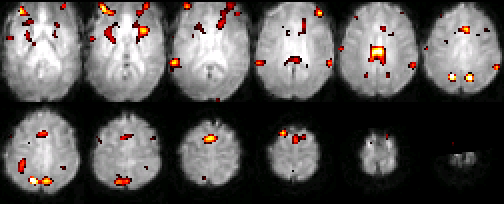

In addition to providing detailed anatomical maps, MRIs can also localize changes in metabolic activity through a subtle tissue response known as the BOLD (Blood Oxygen Level-Dependent) effect. The BOLD effect refers to a temporary change in blood oxygenation observed within a tissue shortly after it increases its metabolic activity. This effect can be significant within the brain when a portion of it is activated by a mental task. As the vasculature attempts to balance the increased oxygen consumption from the tissue with additional blood flow, it creates a temporary imbalance between oxygen consumption and supply, resulting in higher levels of venous blood oxygenation. Since deoxygenated hemoglobin is normally magnetic, a drop in its concentration results in local changes in magnetic environment that lead to a change in the MRI signal. The changes in MRI signals are very subtle, often requiring numerous repetitions and averaging before a significant difference is recognized. Due to the close association between the BOLD effect and metabolic activity, MRI-BOLD scanning is often referred to as functional MRI, or fMRI. Examples of images obtained with fMRI are shown below in Figure 22.

Figure 22:A typical set of functional MRI images, where an activation map is overlaid on a normalized single subject functional scan. The activation is related to the control of auditory spatial selective attention.